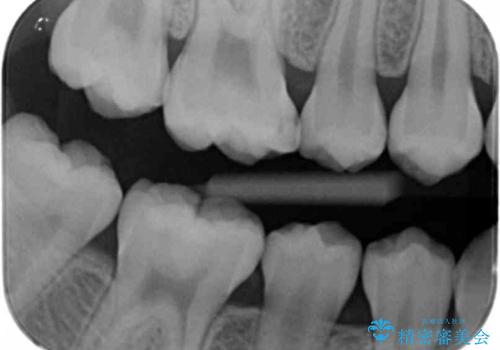

- 検査の結果、レントゲン画像上で虫歯が確認されたため治療をしていくこととなりました。

白くて精度の高いものをご希望されたためセラミックインレーでの治療を行いました。